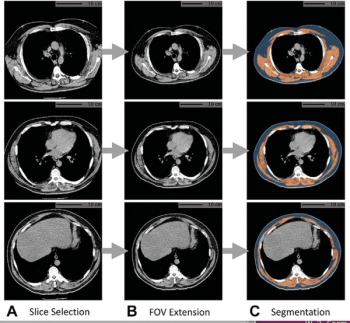

In a study of over 20,700 people, researchers found that artificial intelligence (AI) analysis of body composition measurements via lung cancer screening computed tomography (CT) exams improves the prediction of mortality risks for lung cancer, cardiovascular disease, and all-cause mortality.